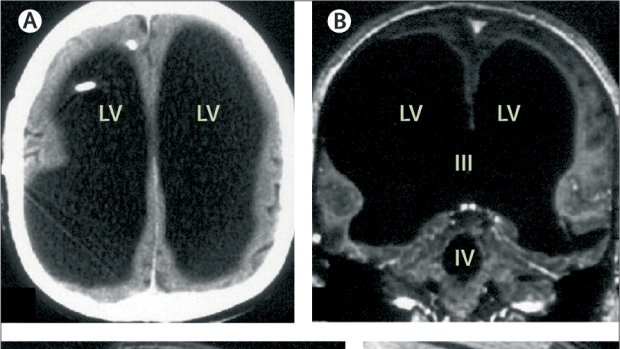

No existing scanner can measure the pattern of connectivity among your neurons, or connectome, as it’s called. MRI machines scan at about a millimeter resolution, whereas synapses are only a few microns across. We could kill you and cut up your brain into microscopically thin sections. Then we could try to trace the spaghetti tangle of dendrites, axons, and their synapses. But even that less-than-enticing technology is not yet scalable. Scientists like Sebastian Seung have plotted the connectome in a small piece of a mouse brain, but we are decades away, at least, from technology that could capture the connectome of the human brain.